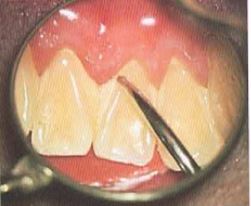

肉眼では確認できない歯肉のわずかな変化も、顕微鏡の拡大視野では見逃さずにチェックできます。

通常歯肉縁下(歯ぐきの中)の歯石除去は目に見えない部位として、手指の感覚で歯石や根面の形態をつかむ練習を行ってきていましたが、顕微鏡で拡大することで縁下歯石を確認しながら除去することができます。